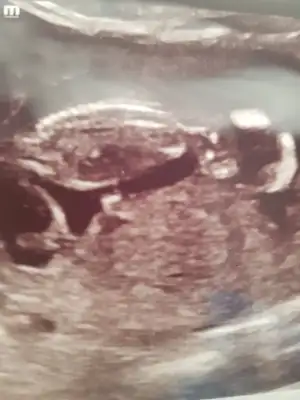

12+4..tahmininizi bekliyorum..

Eklentiler

• 20201022_181417.webp

20201022_181417.webp

32,1 KB · Görüntüleme: 91